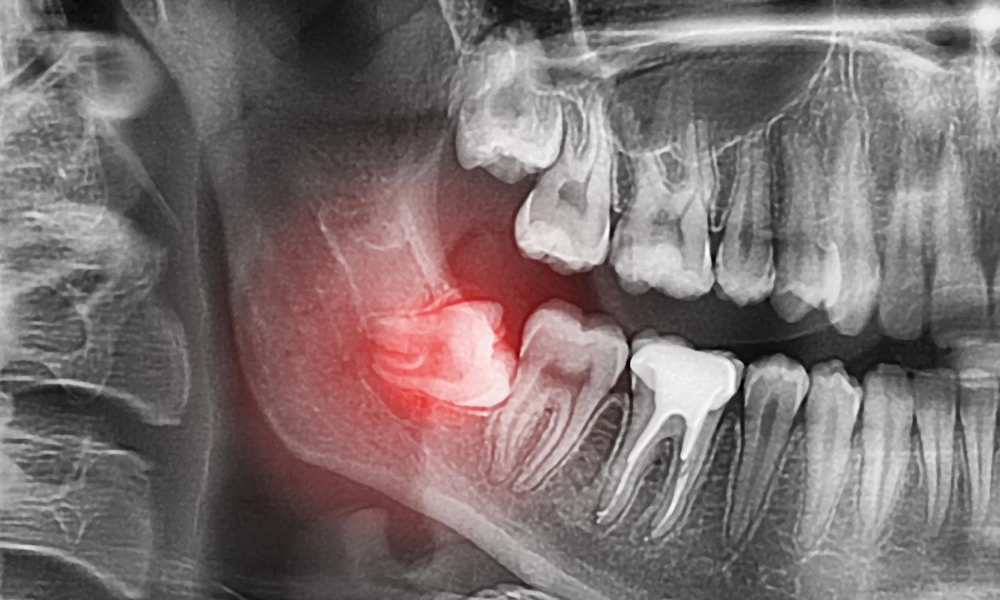

Nếu không mọc bình thường, răng số 8 sẽ mọc ngược hướng xương hàm, đâm thẳng vào răng hàm lớn thứ 2. Khi đã mọc lên được khỏi lợi sẽ không mọc nữa và ngừng phát triển vĩnh viễn.

Khi răng khôn mọc không đúng vị trí, mọc lệch đi sẽ gây ra những triệu chứng khác làm ảnh hướng đến sức khỏe và gây khó chịu, một vài những bất lợi do răng khôn gây ra bao gồm:

Răng số 8 mọc ở phía trong cùng của hàm, nên khi vệ sinh răng miệng sẽ khó làm sạch thức ăn bám trong răng, từ đó tạo điều kiện cho vi khuẩn phát triển. Ngoài ra, trường hợp răng khôn chỉ mọc lên một phần hoặc mọc lệch đâm vào răng kế bên, có thể gây sâu răng và nhiễm trùng, gây đau nhức và khó chịu.